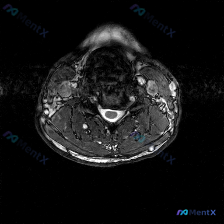

分享一张颈椎MRI T2轴位片,整理了完整的读片和分析思路,大家一起讨论看看。 病例基本影像信息 这是一张颈椎椎间盘水平的T2加权轴位图像,图像对比度良好,脑脊液呈高信号,脊髓中等信号,椎间盘中低信号,没有明显严重伪影,解剖层次清晰。 系统观察各个结构: 1. 骨骼关节:椎体形态完整,椎体后缘可见轻...

刚整理了一份很有启发的颈椎MRI读片病例,核心问题是“这张图里能观察到椎间盘病变吗?”,把完整分析思路分享给大家。 影像基本信息 这是一张颈椎MRI轴位T2加权图像,我们先把观察到的结构特征理清楚: 1. 椎体与椎管:脑脊液呈高信号,脊髓居中,形态规整,内部没有明显异常信号(无水肿灶);椎体后缘有轻...

整理了这张颈椎MRI读片病例和完整分析思路,分享给大家一起讨论 病例与影像基础信息 本次读片对象为颈椎MRI-T2序列轴位单张影像,核心问题是观察图像是否存在椎间盘病变: 1. 影像质量良好,对比度清晰,脊髓、脑脊液、软组织结构显示清楚,无明显运动伪影,扫描层面为颈椎中下段水平 2. 核心影像表现:...